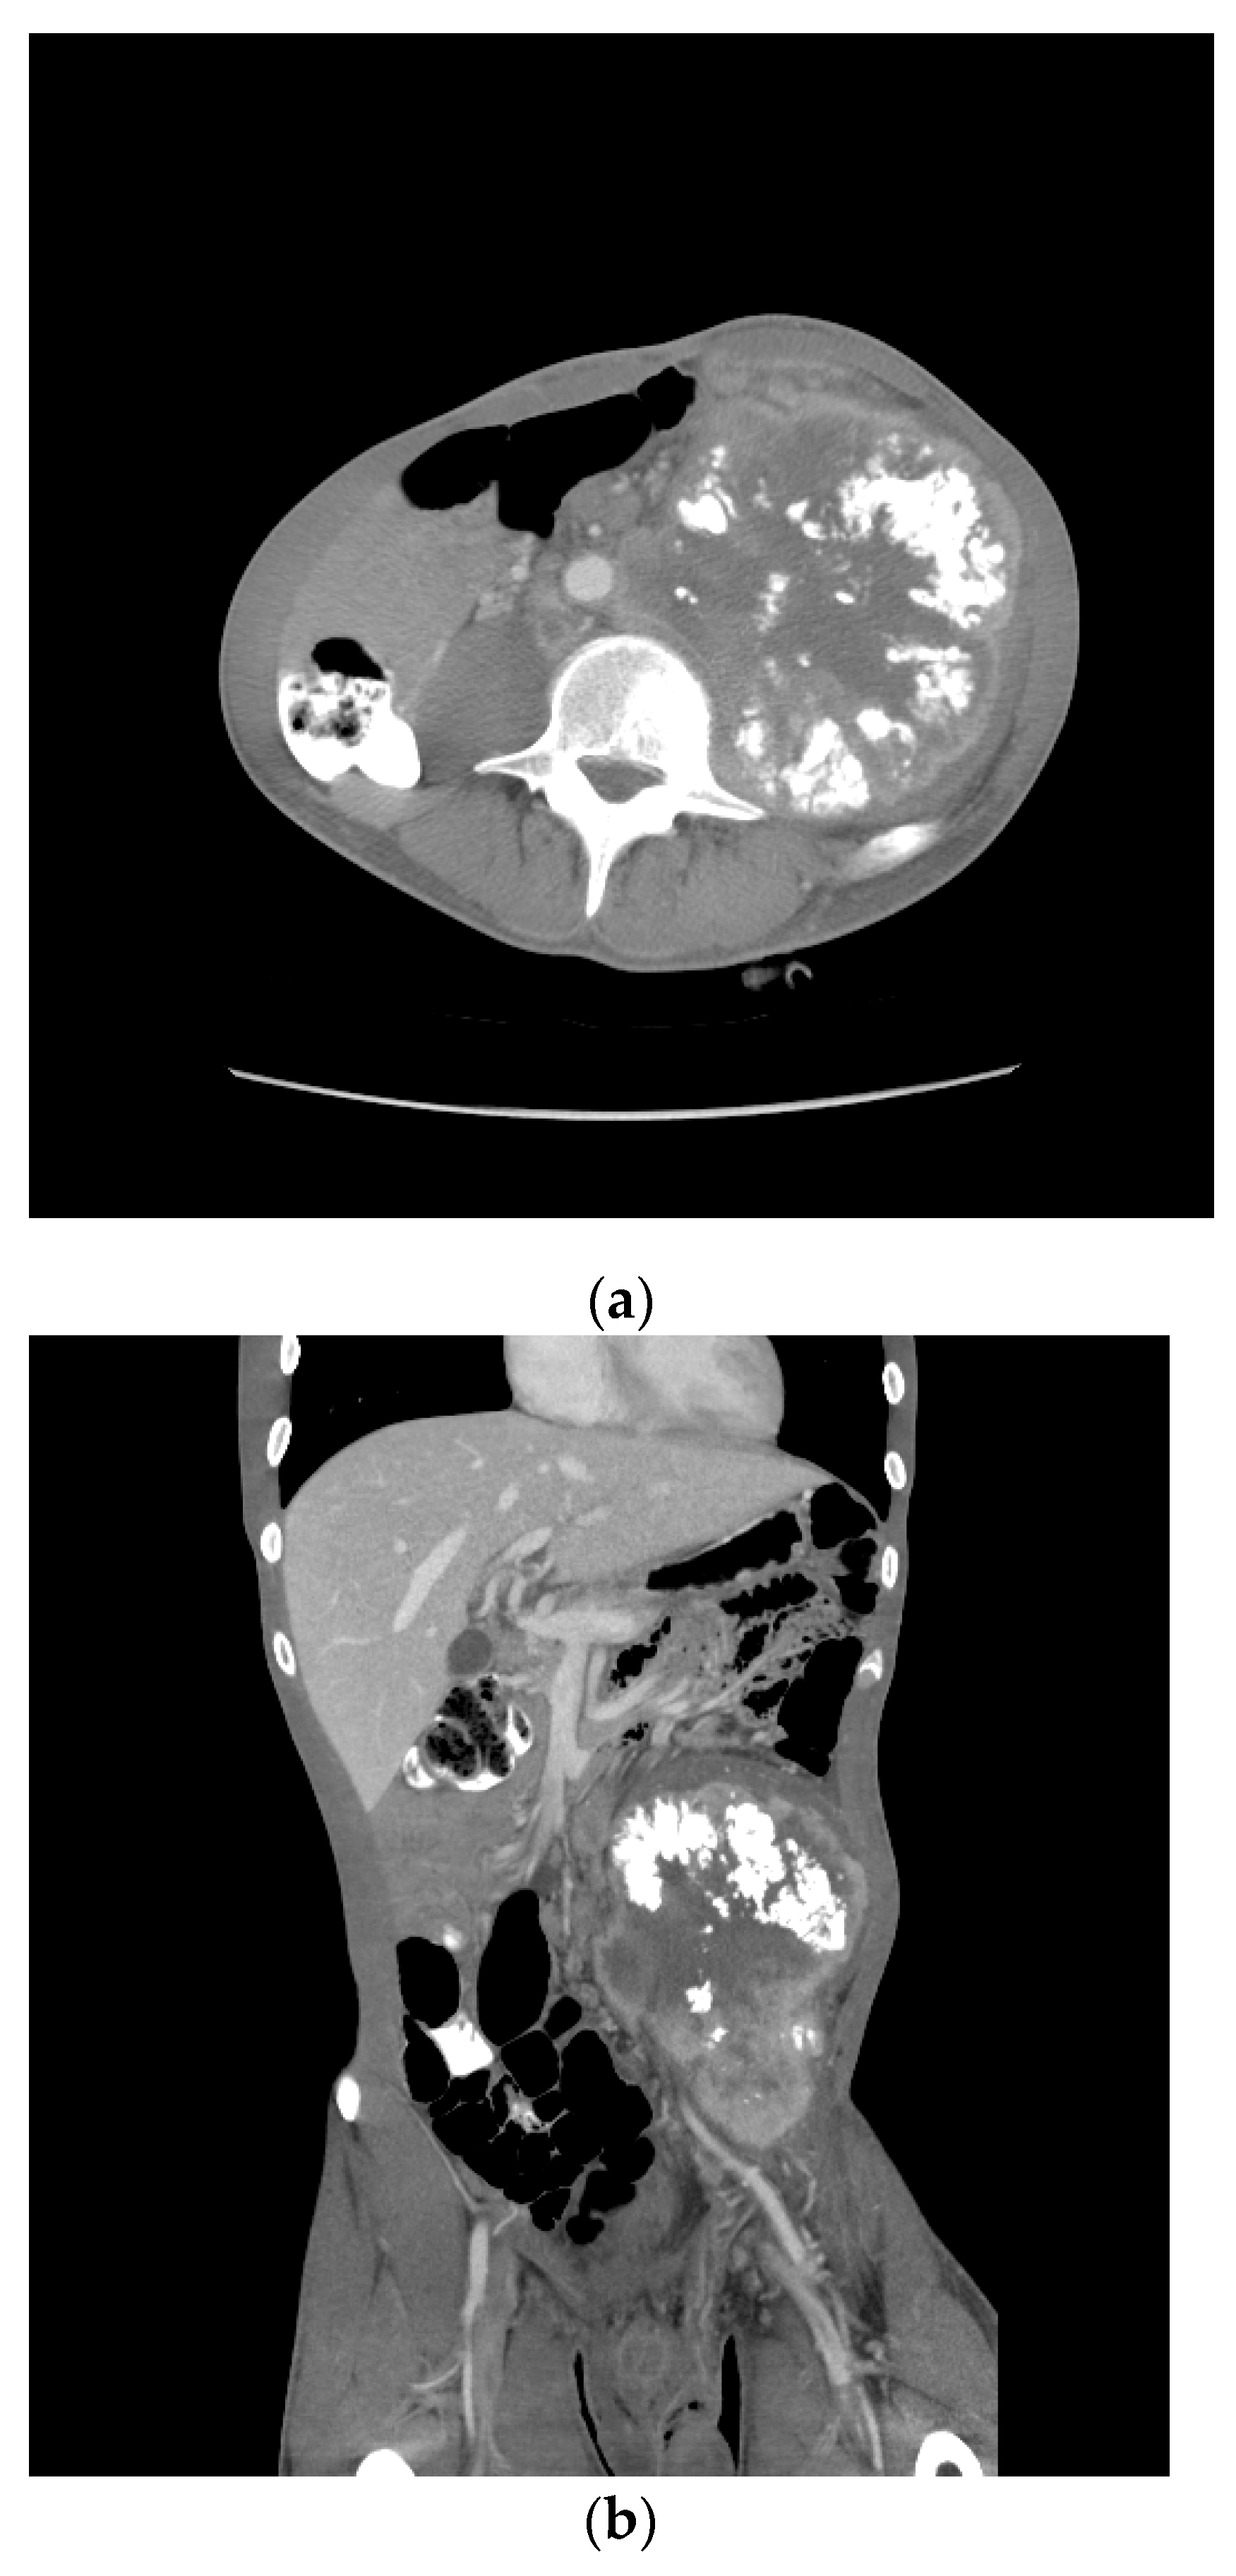

One month later, he received two cycles of BEP without benefit. Four months after the initial therapy, he received capecitabine and oxaliplatin (XELOX), again without benefit. By then, the retroperitoneal mass had increased in size from 12 to 18 cm over the past year. Eight months following the initial diagnosis, his AFP was 205.3 ng/mL, HCG 4.4 mIU/mL, LDH 385 U/L. A CT scan showed a bulky left psoas mass, multicompartmental lymphadenopathy involving bilateral retroperitoneum, left common iliac, left pelvic, left gonadal, and inferior mesenteric chains without overt solid organ metastasis (Figure 6).

Figure 6.

Patient S-YST 2 with bulky calcified lymphadenopathy ((a) transverse and (b) coronal sections).